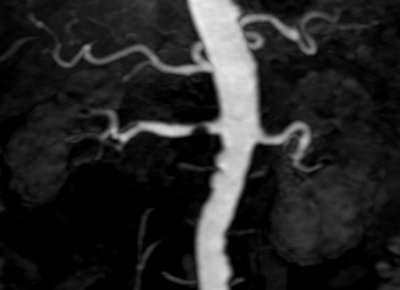

![]() |

| Above, high-resolution contrast-enhanced renal MRA with inadequate depiction of the segmental renal branches. Below, noncontrast Time-SLIP renal MRA depicting the main renal artery, as well as the segmental branches. Images courtesy of Toshiba America Medical Systems. |